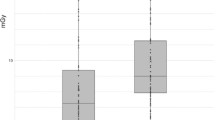

Radiation dose

Table 3 and Fig. 1 provide data on radiation dose for both groups. In group A, median selected tube voltage was 100 kV (90 kV; 100 kV) and mean selected tube current time product 213.6 ± 39.4 mAs (199.7–227.6 mAs), while group B was characterized by a median selected tube voltage of 100 kV (100 kV; 120 kV) and a mean selected tube current time product of 259.0 ± 45.4 mAs (241.0–277.0 mAs) (p < 0.001). Minimum and maximum values of selected tube voltage were 80 kV (n = 1, group A) and 130 kV (n = 3, group B).

Mean values of CTDIvol, SSDE and DLP were 7.58 ± 1.84 mGy (6.92–8.23 mGy), 7.99 ± 1.78 mGy (7.36–8.62 mGy) and 363.7 ± 101.5 mGy * cm (327.8–399.7 mGy * cm) for group A, and 12.60 ± 3.74 mGy (11.12–14.07 mGy), 10.99 ± 2.55 mGy (9.99–12.00 mGy) and 630.6 ± 182.4 mGy * cm (558.5–702.8 mGy * cm) for group B (p < 0.001).

Using a 40 cm normalization, mean values for DLP and ED were 303.8 ± 73.9 mGy * cm (277.6–329.0 mGy * cm) and 5.16 ± 1.26 mSv (4.72–5.61 mSv) in group A in comparison to 521.2 ± 157.1 mGy * cm (459.1–583.4 mGy * cm) and 8.86 ± 2.67 mSv (7.80–9.92 mSv) in group B (p < 0.001).

Regarding the total study population (n = 60), we observed a significant positive correlation between BMI and ED (rs = 0.583, p < 0.001).